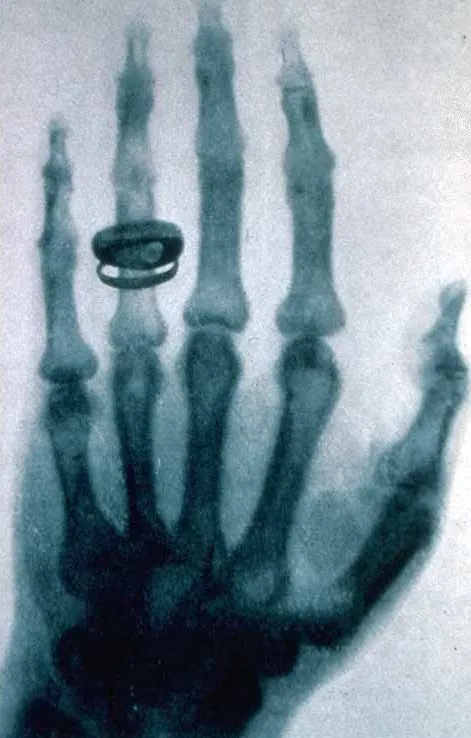

Первый рентгеновский снимок